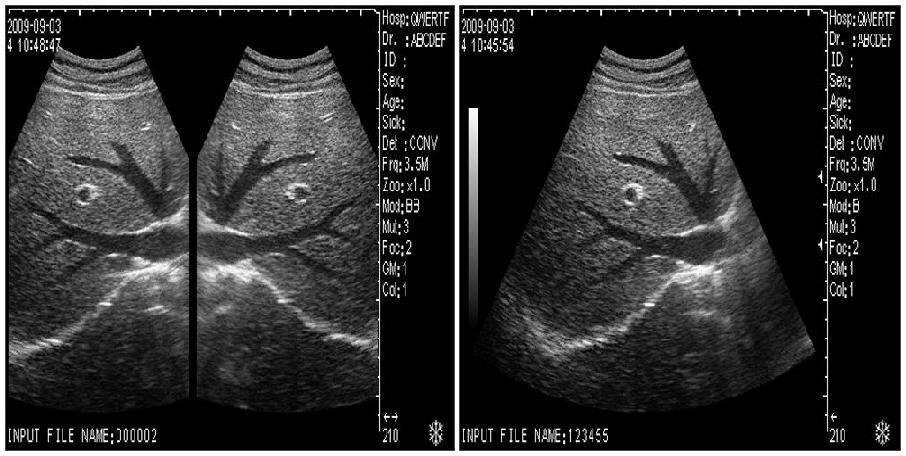

Model: RUS-9000F

Optional: 3.5MHz R60 convex probe

7.5MHz linear probe: 6.5MHz Trans-vaginal probe

Display /Monitor / Screen: 10.1-inch high-resolution TFT LCD

5.0MHz Micro-convex probe: Video Printer Sony UP-897

Probe frequency: Probe frequency

Detectable depth: â¥160mm: Blind area: â¤5mm